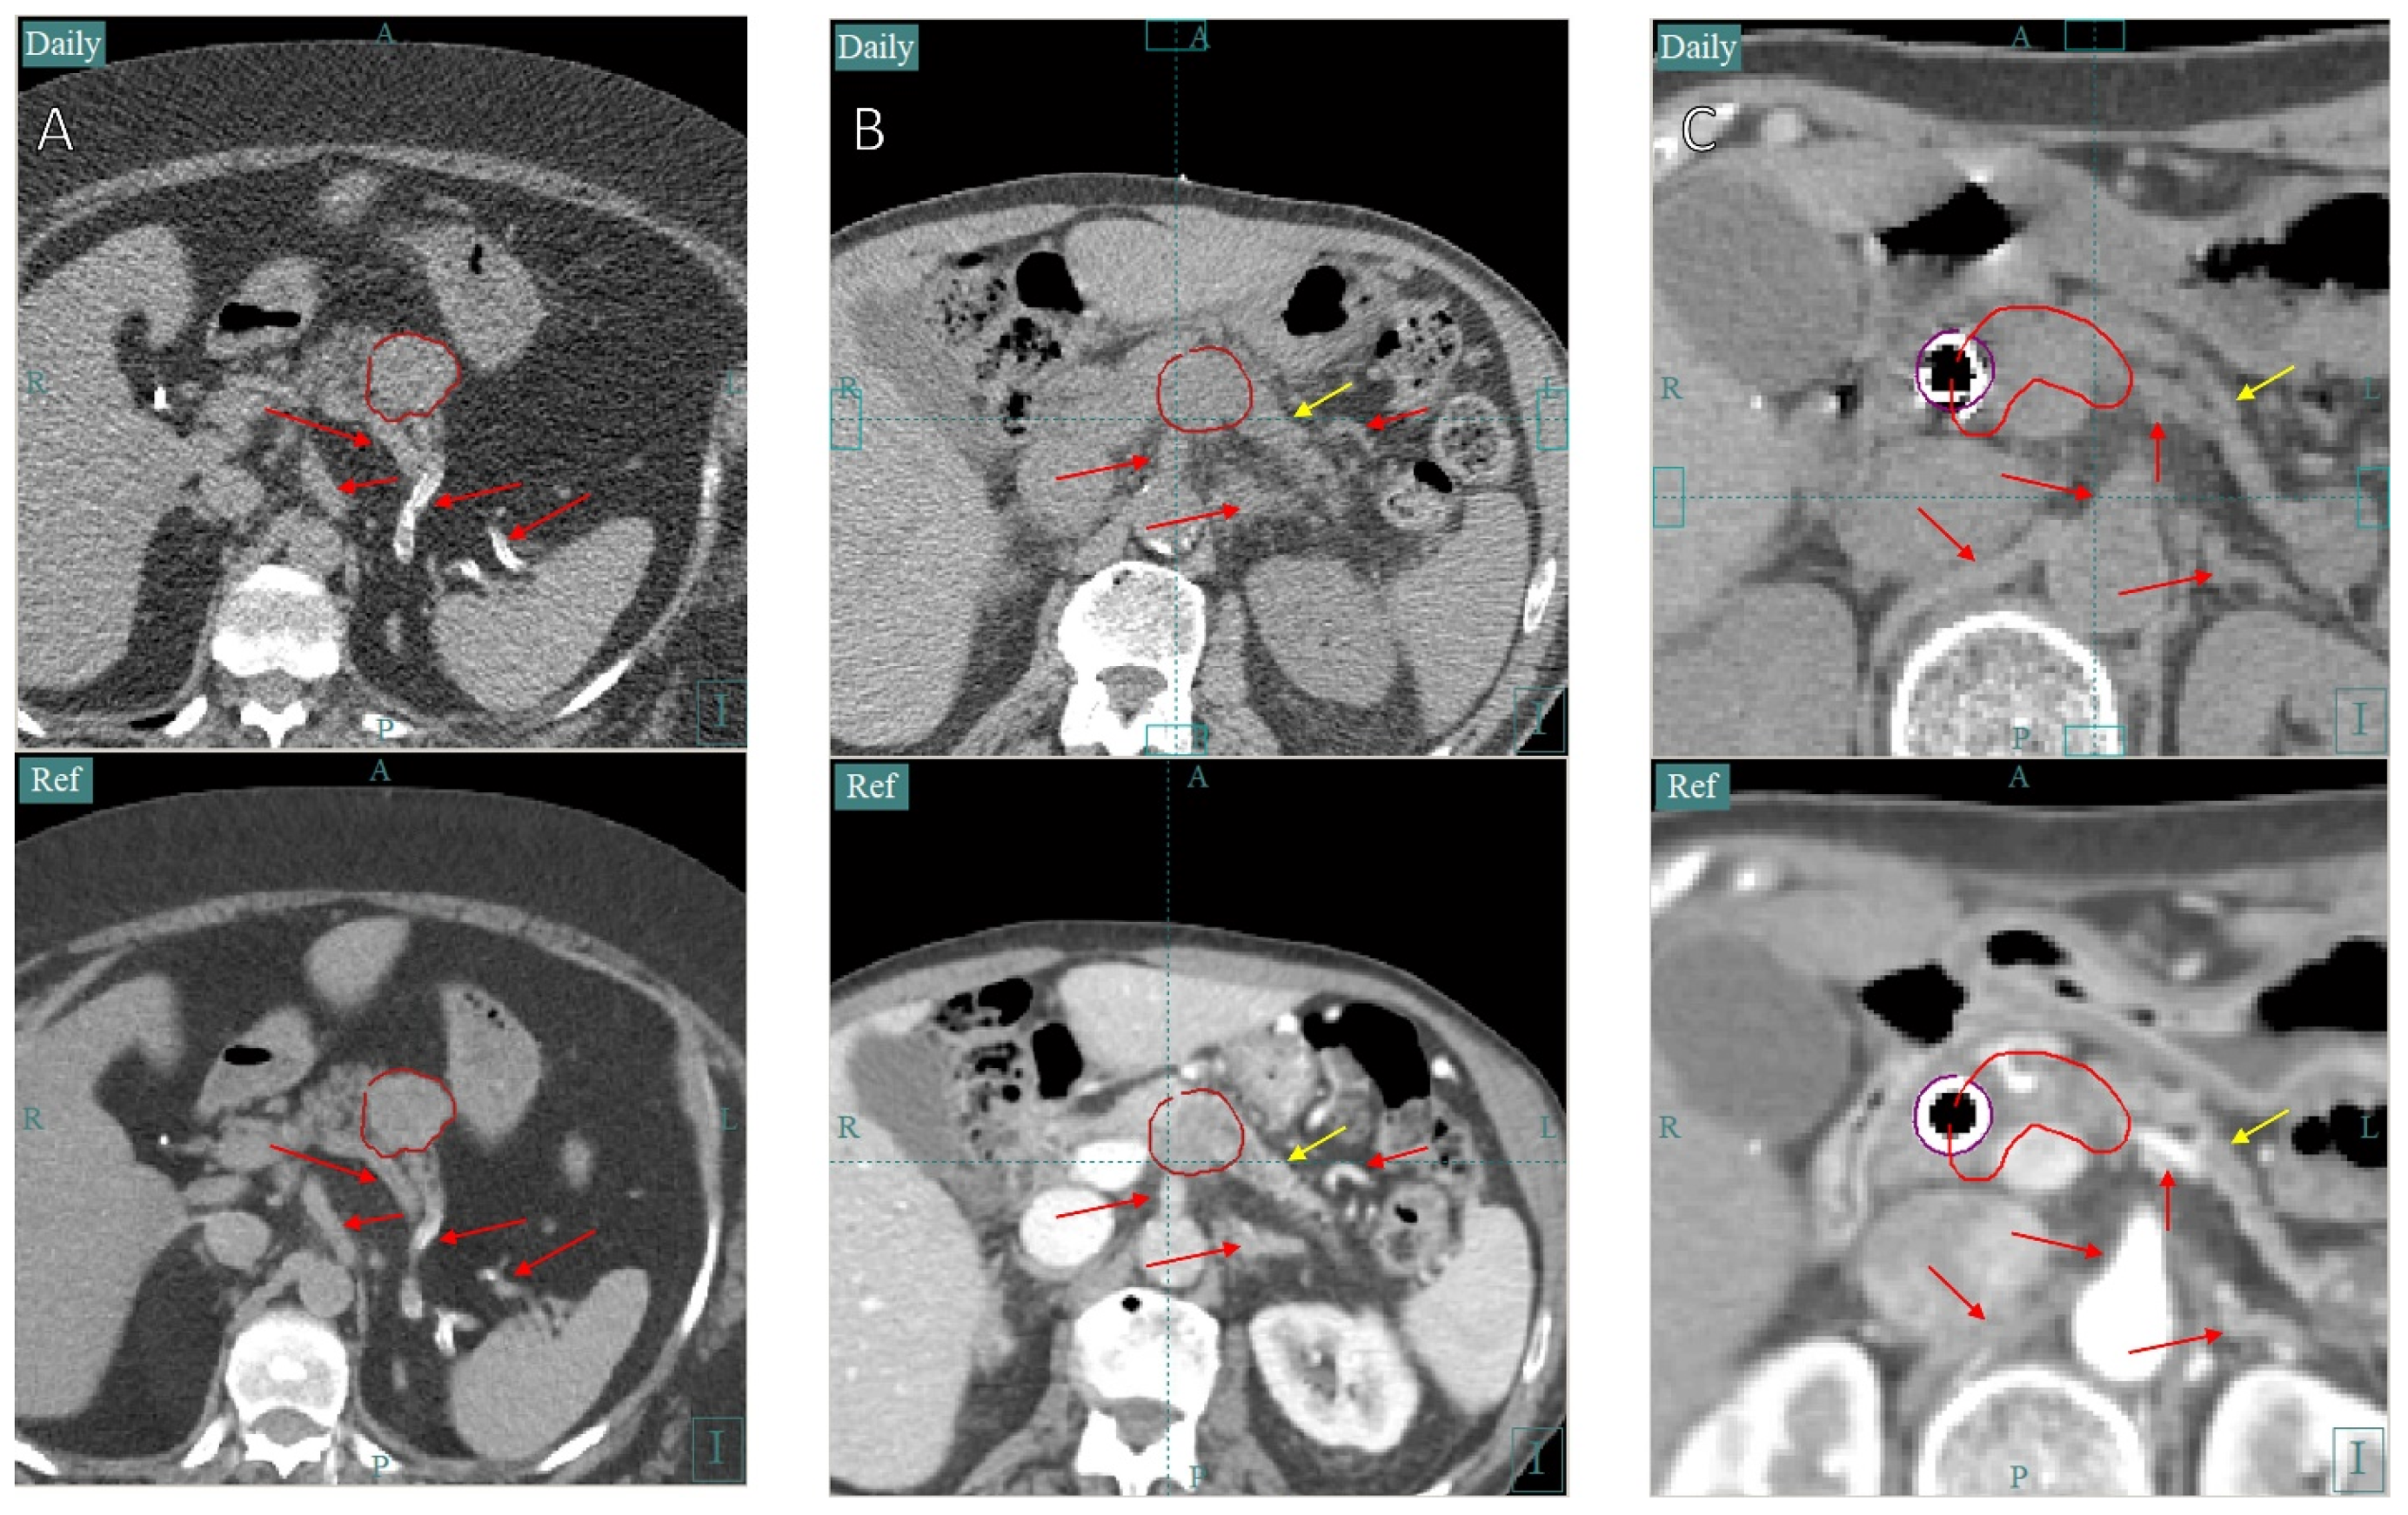

3.2. Case Study 2